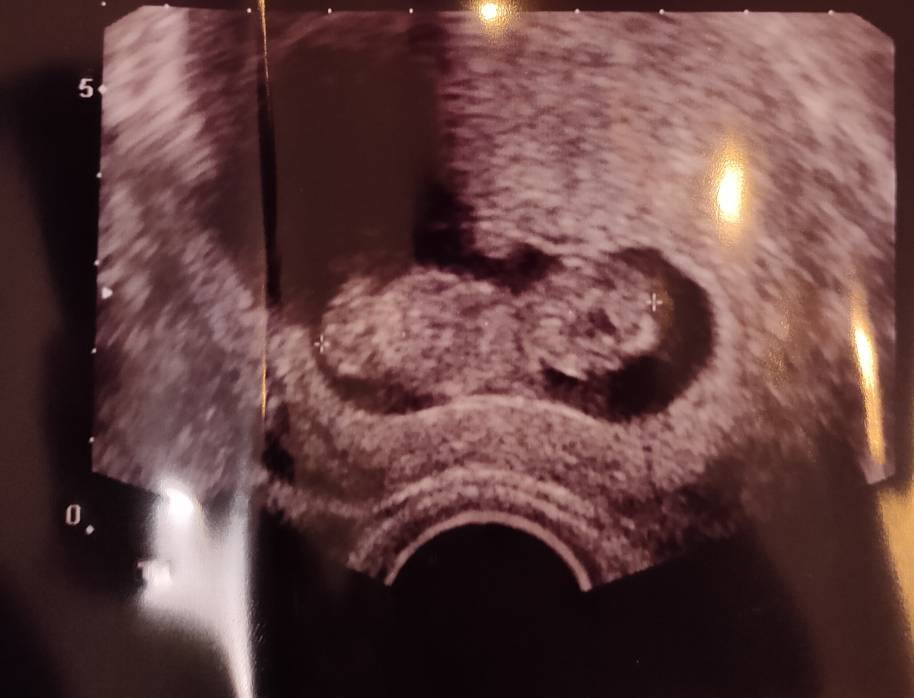

Trzymaj się kochana , jesteśmy z Tobą i życzymy zdrówka dla Was. Musi być dobrze !Jestem po wizycie ginekologicznej. Krwiak się sporo zmniejszył. Z maluszkiem ok. Krwawienie jest ale dużo mniejsze. Muszę cały czas leżeć takie dostałam zalecenia. Prawdopodobnie cała sytuacja wydarzyła się dlatego, że delikatnie współżyliśmy. Dostałam kolejną kroplówkę